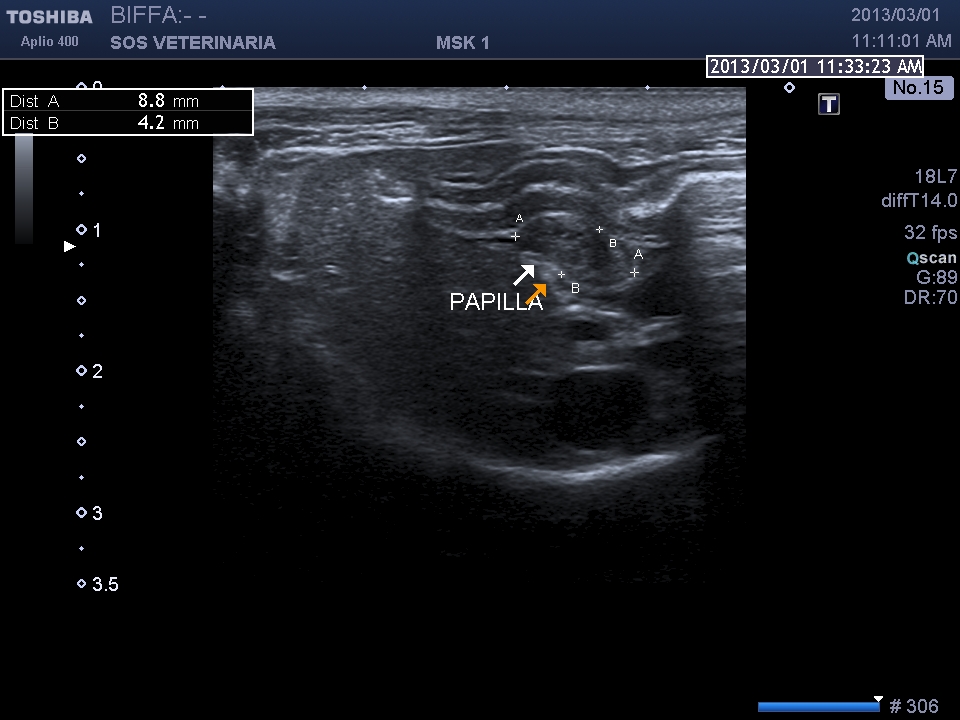

“Diverse scansioni possono essere utilizzate allo scopo di visualizzare le vie biliari extraepatiche: attraverso sezioni trasversali ed oblique a livello dell’11°-12° spazio intercostale destro, tramite scansioni ventrali longitudinali e trasversali, o attraverso la scansione cranioventrale obliqua destra (Santilli R.A. e coll., 1993; Léveillé R. e coll., 1996). Come per il condotto cistico, nella valutazione ecografica del coledoco è possibile osservare: -il diametro, che nei soggetti sani risulta ≤ 4 mm nel gatto, mentre nella specie canina misura 1-3 mm; -la forma; -il contenuto; -l’ecogenicità e lo spessore della parete (Gaillot H.A. e coll, 2007; Léveillé R. e coll, 1996; Brinkman-Ferguson E.L. e coll., 2009).

Durante l’esame delle strutture biliari può venire identificata la papilla duodenale le cui dimensioni, nei gatti sani, variano dai 2,9 a 5,5 mm in larghezza ed una massima altezza di 4,0 mm, in sezione trasversa; nel cane le sue dimensioni sembrano essere maggiormente variabili, in relazione alle differenze di peso e di razza (Center S.A., 2009).”

scansione trasversale papilla

scansione sagittale paipilla